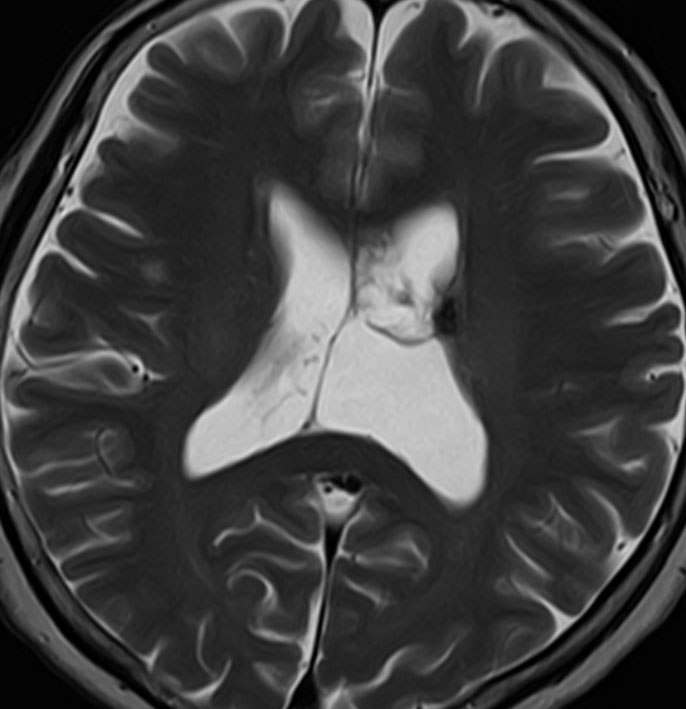

20代の男性の神経細胞腫です。側脳室の中のとても大きな腫瘍です。上段はガドリニウムという造影剤を入れた時のMRIです。下段の中央はCTですが,石灰化が見られます。脳外科の先生には,この脳室内腫瘍は一見transcallosal approach(経脳梁到達法)という手術で取れるように見えるかもしれませんが,そうではなくて,脳室の壁とくに上壁と側壁にくっついているのでなかなか取れません。この患者さんの場合は右の頭頂葉というところからtranscortical approach(経皮質到達法)で全摘出しました。後遺症もなく再発もなく術後10年が過ぎています。全部とれれば治ってしまう腫瘍です。